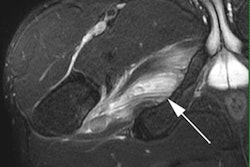

Coronal proton density-weighted MR image shows femoroacetabular impingement of the cam type. "Bump" from bone formation at the femoral head/neck junction (white arrow) with full-thickness articular cartilage defects of acetabulum (black arrow) and labral tear (red arrow). All images courtesy of Dr. Patricia Cunningham.Please give a detailed overview of the sports injuries with which you are most familiar and their respective modalities.